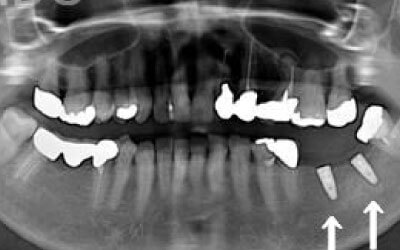

最も大きな違いは、前後の歯の寿命に影響を与えることです。

ブリッジでは、抜けた歯の前後の歯を大きな虫歯と同じくらいまで削らなければならず、

また、抜けた歯の代わりに前後の歯がその力を支えるため、常に1.5倍の負荷がかかります。

1)ブリッジ

2)歯を大きく削る+支えの歯に1.5倍の力がかかる

3)前後の歯の寿命が著しく減る

ブリッジの支えの歯は、データでは10年以内に68%が抜歯になります。